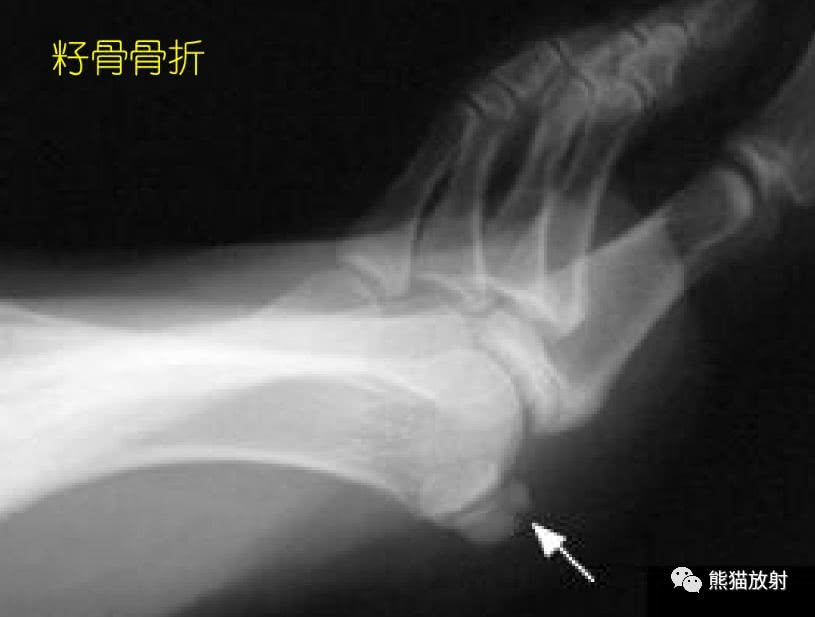

032期 】2016-01-19 . 籽骨、副骨、永存性骨骺

籽骨、副骨及永存骨骺,请别再误诊!_搜狐其它